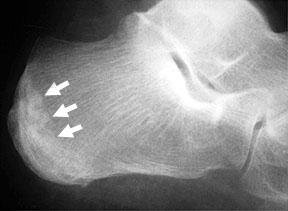

these arrows show the evidence calcaneal stress fracture. while there is no crack present there are calcium deposits where the bone has repaired itself.

stress fractures of the heel can be diagnosed by cupping the heel with the hand(s) and applying side-to-side pressure,

which induces pain. Antalgic, propulsive gait is normally seen with splinting of the heel in either varus or valgus in an attempt to keep pressure off the fracture site. In some cases the patient will plantar-flex the ankle joint and flex the hip and knee joints as a form of

compensation to avoid heel strike. Muscle spasm can be seen in many of these cases, again as a result of efforts to protect the injured Calcaneus